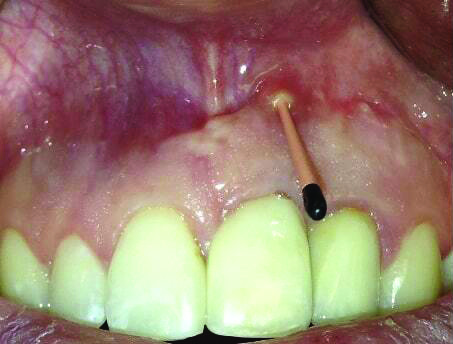

Fig 15 and Fig 16. Case 2: Clinical view (Fig 15) and radiograph (Fig 16) at 12-month follow-up confirming resolution of the peri-implant defect.

Fig 16. Case 2: Clinical view (Fig 15) and radiograph (Fig 16) at 12-month follow-up confirming resolution of the peri-implant defect.

The 12-month and 7-year follow-ups for case 2 showed similar improvements with normal soft-tissue healing and bone fill and normal pocket depths at 12 months (Figure 15 and Figure 16) and 7 years post-treatment (Figure 17 and Figure 18) (Table 1).